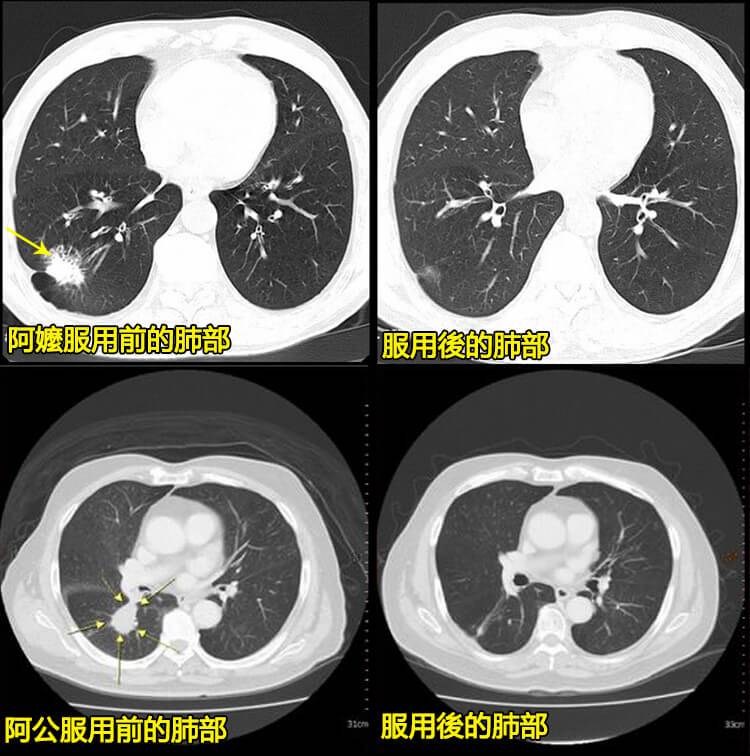

七天肺部黑塊完全消失

從不能做任何活動到能上街買菜僅用了55天

陳阿嬤自述:

本人得肺氣腫已經近20年了,剛患病時,只是咳嗽氣短,再加上年輕時家庭條件不好,為了供子女上學,期間也就自己吃點藥維持著,這一拖,就 拖了近20年! 近幾年,隨著年齡的增大,發病的次數越來越頻繁,病情也越來越重,除了咳嗽咳痰之外,總感覺乏力,食慾也越來越差,嗜睡和氣喘也越來 越厲害,多走幾步就喘的不行,胸口總是憋悶的難受,而且還疼的厲害,還總是莫名的心慌,徹夜難眠,為治病輾轉多地,依舊求醫無果! 在朋友的推薦下開始服用陳晉興醫師的(日本清肺靈芝),在吃了一個療程後,呼吸越來越順暢了,胸痛,浮腫、心率加快,心律不齊的症狀明顯改善,第二個療程的時候睡眠品質提高了,人精神了很多,服用到第三療程的時候幾乎告別老咳喘了,前陣子去醫院一檢查肺氣腫居然康復了,我的主治醫師都感到很驚奇,哈哈!

這是陳晉興主任最新引進,採用最新技術,可解決肺部情況。此臨床試驗數據表明,【日本清肺靈芝】可以幫助呼吸道疾病患者治愈率高達98%以上,獲得了高度認可